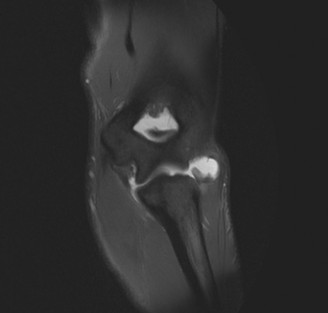

While plain films confirm the presence of osseous reactive changes, Magnetic Resonance Imaging (MRI) is indispensable for evaluating the articular cartilage, the integrity of the UCL, and the presence of occult loose bodies. A high-resolution MRI, preferably an MR Arthrogram (MRA) if subtle UCL pathology is suspected, provides a comprehensive map of the elbow's soft tissue envelope.

In this case, the MRI demonstrates focal chondromalacia and subchondral edema at the posteromedial olecranon tip and the corresponding medial wall of the olecranon fossa—the classic "kissing lesion" of VEO. Crucially, the anterior bundle of the UCL appears continuous and intact, with no evidence of high-grade partial tearing, T-sign (contrast leakage beneath the distal insertion), or severe attenuation. The flexor-pronator mass and the ECRB origin are pristine.